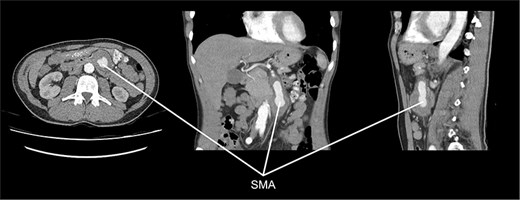

Initial workup included esophagogastroduodenoscopy, which showed no abnormalities. A computed tomography (CT) angiography (Fig. 1) revealed a 56-mm SMAA, with a perfused segment measuring 23 mm in diameter and 58 mm in length. The aneurysm’s proximal segment exhibited significant stenosis due to thrombosis, beginning 21 mm distal to its origin from the aorta. Given the risk of rupture or ischemic complications, intervention was indicated. Open surgical repair was chosen over endovascular treatment because the aneurysm involved multiple SMA branches, making stenting unsafe due to the high ischemic risk.